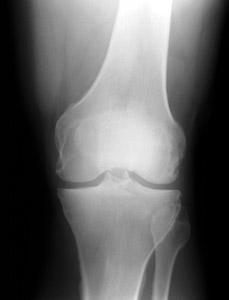

AP view | |

Fractures of the patella can be confused with bipartite or multipartite patella. The radiographs below

show bipartite patella. Compare the images below with those shown above. Notice that the fractured

patella has pieces that fit together like a jigsaw puzzle. The bipartite or multipartite patella has

pieces with more rounded margins that do not fit together. | ||